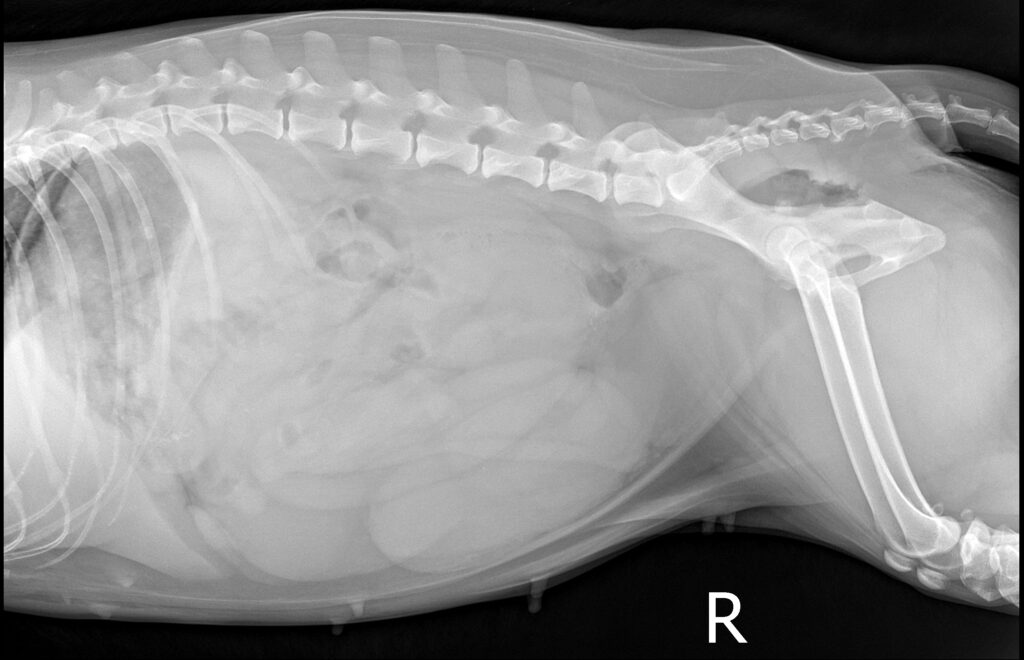

복부 방사선 검사 결과 / 출처: 24시온숲동물의료센터

복부초음파·방사선검사 결과

- 내원 당시 시행한 복부 초음파 및 방사선 검사에서 정상적으로는 4mm 정도 두께인 자궁이 약 4cm까지 심하게 확장되어 있는 모습이 확인되었습니다. 내부에는 고름으로 추정되는 내용물이 가득 차 있었으며, 이는 전형적인 자궁축농증의 소견에 해당합니다.